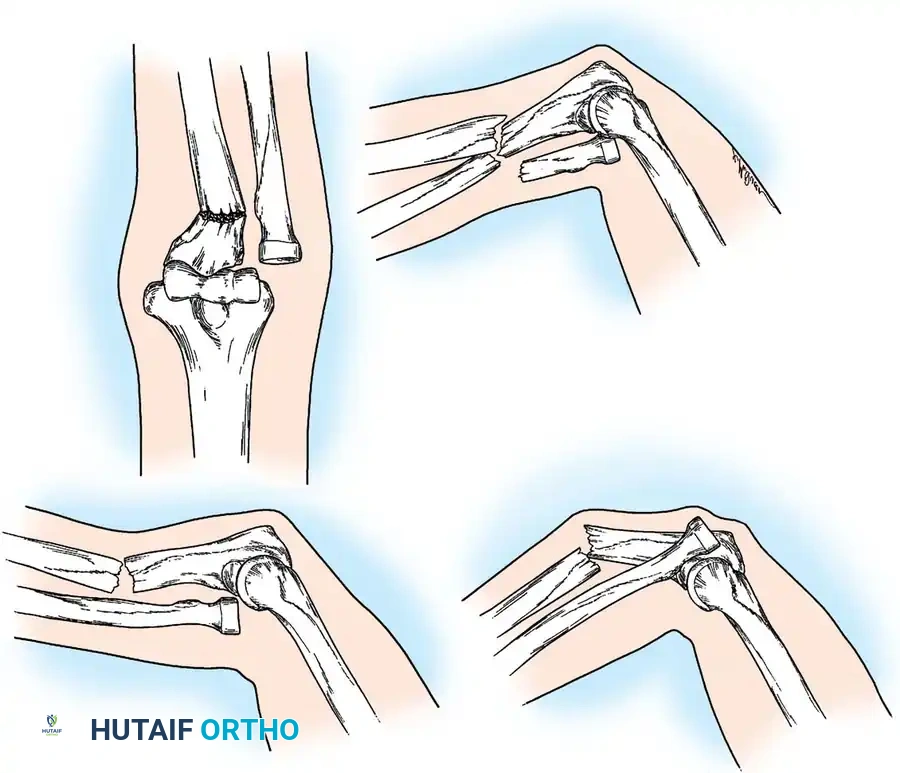

Classification of Olecranon Fractures

Schatzker classified olecranon fractures based on the fracture pattern and the mechanical considerations dictating the required type of internal fixation. Understanding this classification is paramount for preoperative planning.

Fig. 54-52 A-F, Schatzker classification of olecranon fractures. (From Browner BD, Jupiter JB, Levine AM, et al, eds: Skeletal trauma, Philadelphia, Saunders, 1992.)

The Schatzker classification includes:

* Transverse: Typically avulsion injuries amenable to tension band wiring.

* Transverse-Impacted: Requires elevation of the impacted articular segment and bone grafting before fixation.

* Oblique: May require lag screw fixation in addition to a neutralization plate or tension band.

* Comminuted: High-energy injuries often requiring plate osteosynthesis to prevent shortening of the greater sigmoid notch.

* Oblique-Distal: Fractures extending distal to the coronoid process, compromising elbow stability.

* Fracture-Dislocation: Complex injuries requiring rigid plate fixation to restore the stabilizing buttress of the proximal ulna.